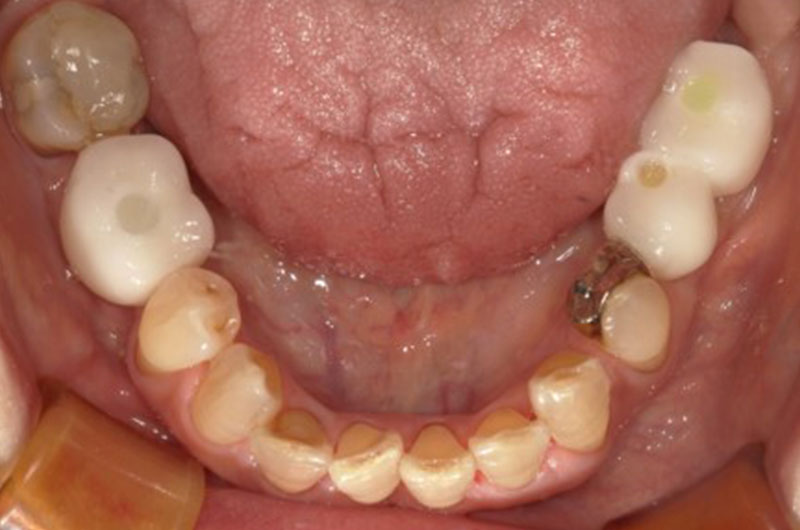

症例5

| 治療ケース | 下顎:オールオン4 歯科麻酔科医管理下にて静脈内鎮静・局所麻酔を行い、4本のインプラントを埋入し即時負荷。当日中に12本のプロビジョナル(仮歯)を装着。7ケ月後に上部構造オールセラミック装着。 |

| 症状 | さし歯が取れて入れ歯が合わなくなってしまいました。 |

| 治療結果 | 遠方から、入れ歯が合わないという主訴でご来院。オールオン4で即時負荷を行う事により、当日中にプロビジョナル(仮歯)が装着でき、すぐに食事ができるようになり、大変満足されています。 |

| 治療開始月 | 2022年4月 |

| 治療期間 | 約7ヶ月 |